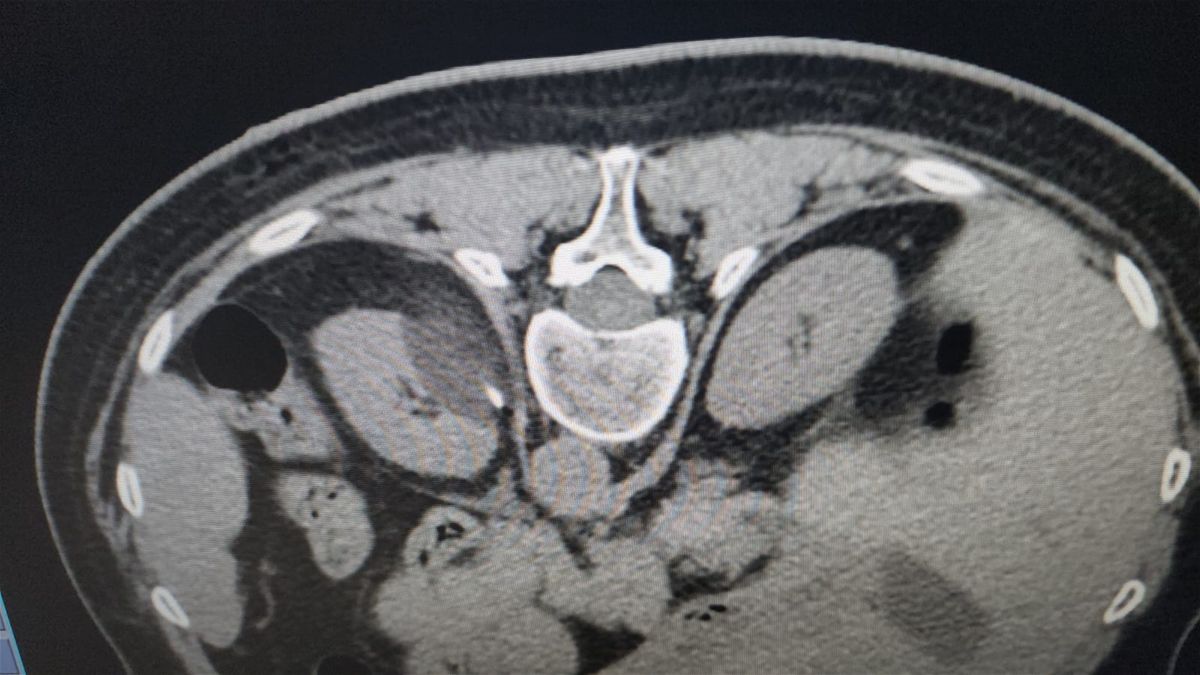

هو عملية استئصال الورم بدون الحاجة إلى "الفتح الجراحي" وخصوصا في حالات المرضى الذين لا يمكن إجراء جراحة لهم. ويُعالج بالتبريد كل حالات السرطان في الأعضاء، بواسطة مسابير لتجميد الأورام والقضاء عليها، وحتما بحسب كل حالة وتشخصيها، الا انّ العلاج بالتبريد يمكن استخدامه مع كافة الأعمار. والجدير ذكره انّ هذا العلاج لا يطبق على الأعضاء الجوفاء في جسم الإنسان كالمعدة والمبولة، بل على الاعضاء غير الجوفاء كالكبد والبروستات والعظم والرئة، وأعضاء أخرى.

فكيف يتم التشخيص والتدخل الطبي؟ يقوم الأطباء بالتشخيص قبل العملية وبعدها بواسطة "الصورة النووية"، ثم تتم المقارنة بين كل المراحل من الناحية التقنية، للوصول الى مرحلة إدخال مسابير التبريد الى مكان الورم، وذلك من خلال ضخ غاز قوي جدا يُسمى غاز "الارغون" بضغط كبير وعبر أجهزة متطورة، وذلك تحت مراقبة مباشرة، ليتم تدمير الأورام عن طريق تجميد نسيج الورم، بدرجة حرارة منخفضة للغاية (تصل إلى 160 تحت الصفر)، باستخدام تقنية التصوير.

يتحدث مدلج عن العلاج مشيرا الى انّ الجراحة بالتبريد هي من أهم التقنيات المستخدمة اليوم في العالم لاستئصال الأورام الخبيثة والحميدة في الجسم. ويقول: "الأهم انّ العملية تتم من دون فتح جراحي، وانما عبر أجهزة متخصصة إضافة الى مسابير التبريد التي تدخل مباشرة الى المنطقة المصابة وتقوم بإنشاء كرة جليدية، هذه الكرة تتدنى فيها الحرارة بالناقص 40 درجة وكفيلة بكي كل الخلايا المتورمة التي يجب اصابتها".